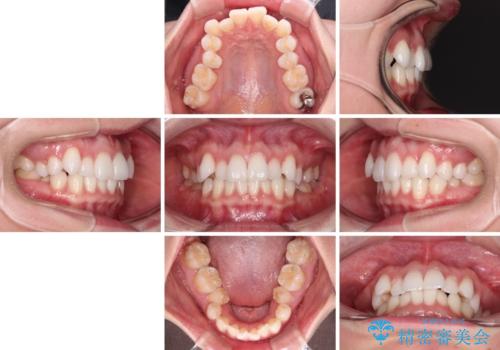

- 上下前歯のデコボコ、特に右上の八重歯を気にして来院された患者様です。

妊娠、出産の予定があり、毎月の通院が困難となる可能性があったため、インビザラインによる矯正治療を行うこととしました。

事前に親知らずを抜歯しておき、出産時期に困ることのないように準備をした上で治療を開始しました。

治療後半では悪阻によりマウスピースの装着時間が不十分となることもありましたが、それよりも前にしっかりと装着時間を守って治療を進めることができたため、特に気になるところなく治療を終えることができました。